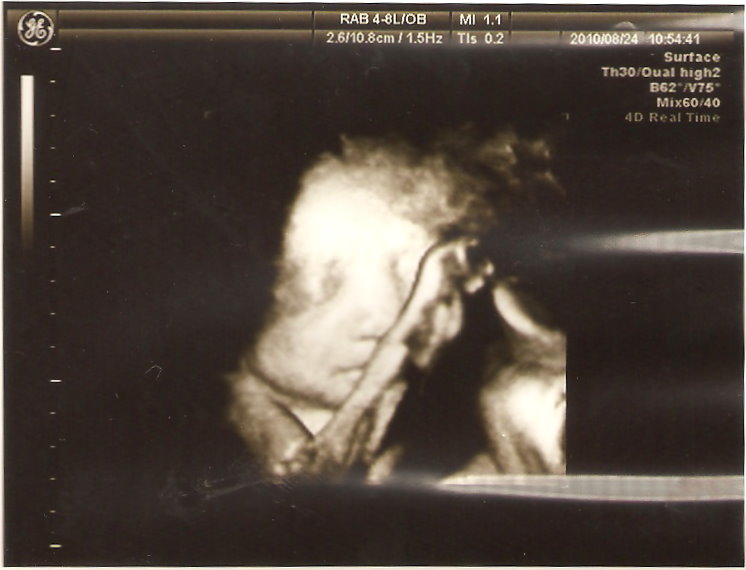

本來都看不太到臉,頭低低又用手遮住臉的臭小子,竟在這個時候被醫生拍到他在微笑

是的,微笑!我跟我姊都很明顯的看到他在笑,真想呼一巴掌給他

不過平常滾得天翻地覆的他檢查時竟然裝乖都不太動,醫生常常用超音波推肚子,還叫他快起來

果然人少時不一樣,上次人太多,看不到就算了,醫生根本沒空等他動啊~